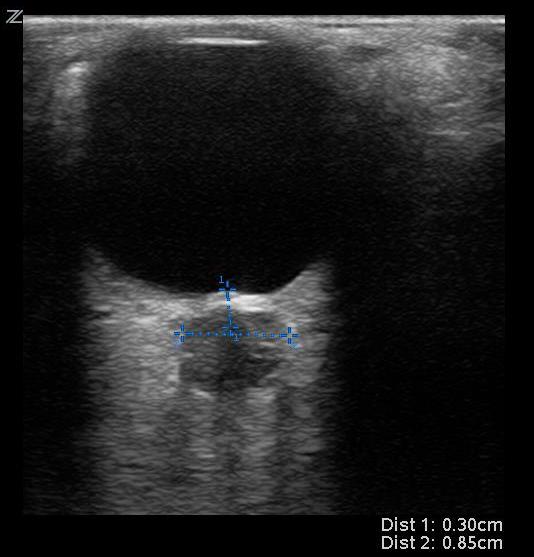

- On ultrasound, a normal optic nerve sheath measures up to 5.0 mm in diameter. The ONSD is measured 3mm posterior to the globe for both eyes.

- A position of 3mm behind the globe is recommended because the ultrasound contrast is greatest, and the results are more reproducible.

- Two measurements are averaged.

- An averaged ONSD > 5 mm in adults is considered abnormal and elevated ICP should be considered.4

- An averaged ONSD > 4.5 mm in children (1-15 years) and > 4mm (less than 1 year of age) are abnormal.4

- Figure 11. Example of increased optic nerve sheath diameter. Optic nerve sheath diameter > 5mm is considered abnormal and should raise concern for elevated intracranial pressure.